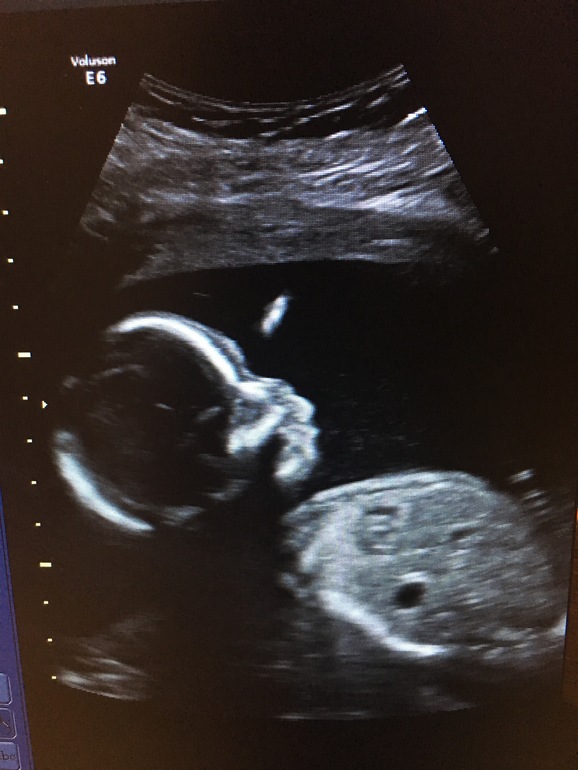

Недавно прошли 2 скрининг.

А вчера нам было ровно 20 недель - экватор! 😱 Казалось это так далеко и долго, а выходит, что такими темпами уже и рожать скоро)

По скринингу всё отлично, единственное, меня смутила шейка матки 36мм. Узистка сказала, что это норма, нооо... у кого так было на моем сроке, что было дальше?

Пинаться наш мальчишка стал сильнее) животик такой уже прям беременный, классно)